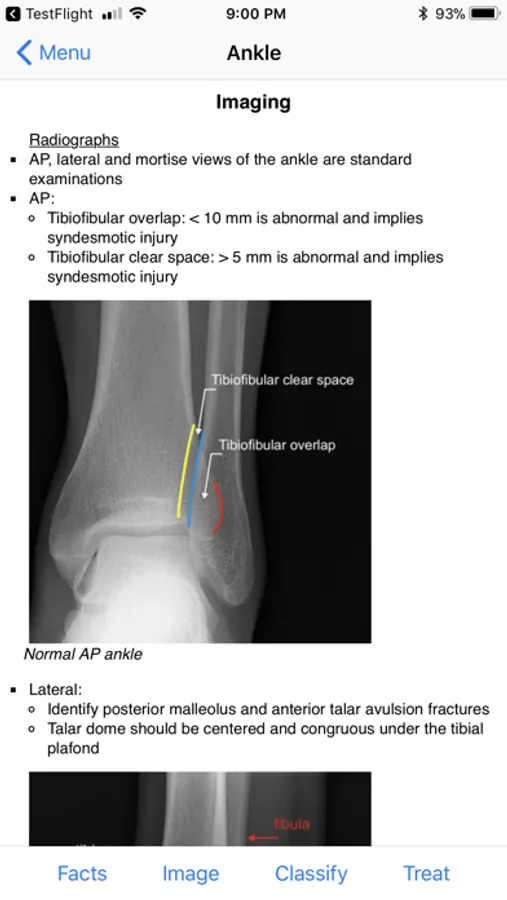

Imaging begins with the standard radiographic examinations for each anatomic region. This is followed by injury-specific views, relevant metrics and findings as well as supplemental modalities.